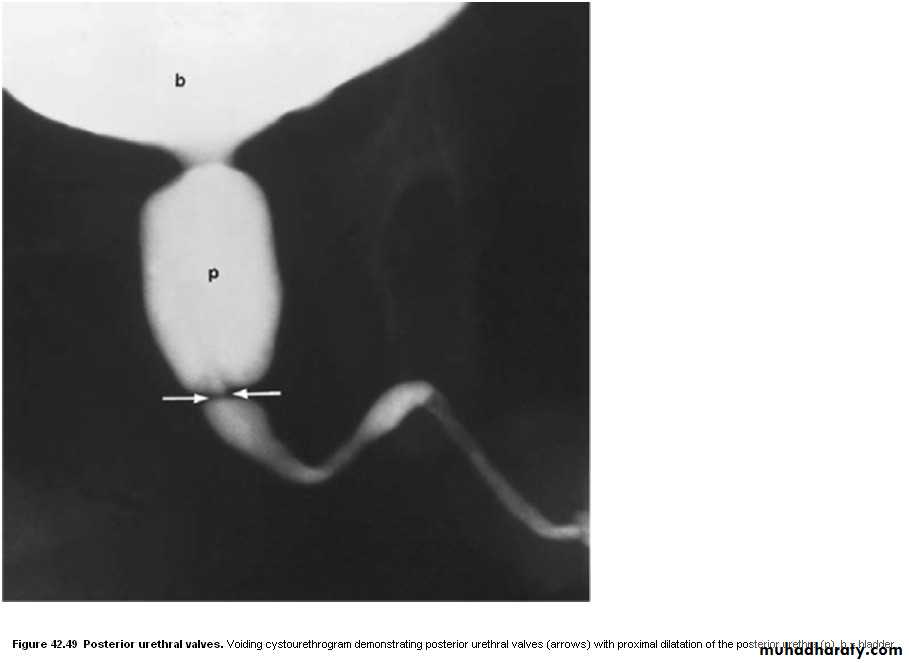

• Posterior urethral valves

• Congenital valves in the posterior urethra in boys are the commonest cause of bladder outflow obstruction in male children. The diagnosis may be first suspected at antenatal US, where there is bilateral hydronephrosis. After birth, US confirms bilateral hydronephrosis and hydroureters and a thick-walled bladder. Urethral valves cannot be demonstrated by retrograde urethrography as there is no obstruction to retrograde flow. They are easily demonstrated at micturating cystourethrography, where substantial dilatation of the posterior urethra is seen which terminates abruptly in a convex border formed by the valves.Urethral strictures